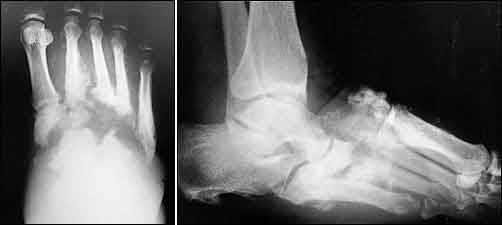

Il piede di Charcot è una complicanza del diabete che colpisce le ossa e le articolazioni del piede. Se non trattato adeguatamente al momento della sua comparsa, provoca la frammentazione delle ossa e una deformazione dei piedi, tali da perdere i normali rapporti articolari. L’architettura del piede viene così fortemente compromessa e il risultato è una grave deformità.

“La prima causa è la presenza della neuropatia diabetica, un’alterazione strutturale dei nervi legata all’iperglicemia cronica” ha spiegato il prof. Dalla Paola. “Su questa neuropatia si innesca un sovvertimento osseo-articolare che provoca deformità tali da procurare ulcere difficilmente guaribili o recidivanti, che alla fine possono portare all’amputazione dell’arto colpito. Le teorie sull’origine di questa patologia sono numerose ma è soprattutto la genesi di tipo infiammatorio locale che, in alcune persone con neuropatia diabetica, spinge l’osso del piede a subire alterazioni che sfociano nel piede di Charcot. I sintomi molto spesso vengono confusi con altre patologie. Un piede gonfio, edematoso, dolente in un diabetico deve far pensare alla neuropatia di Charcot, invece la maggior parte dei pazienti arriva troppo tardi a un centro specialistico”.